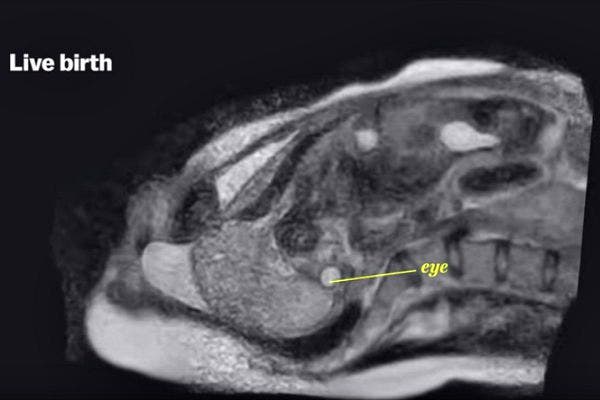

6. Nine months later and out comes a baby.

Since MRI machines are very loud, they stopped the video of the live birth when the baby's head emerged, since they didn't want the noise to damage the baby's hearing.